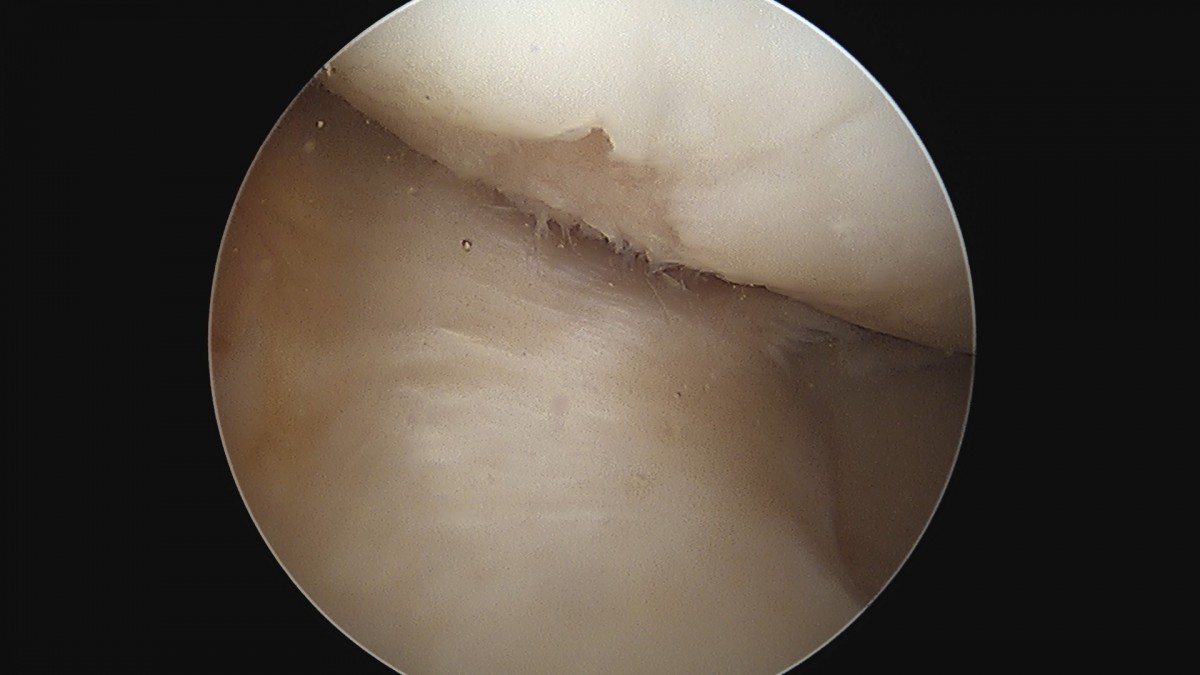

이재상원장님 무릎 반월상 연골판 절제술 안경O 환자

dae765e4d9ac96aee867c9d6292d8784_1758005873_4643.jpg